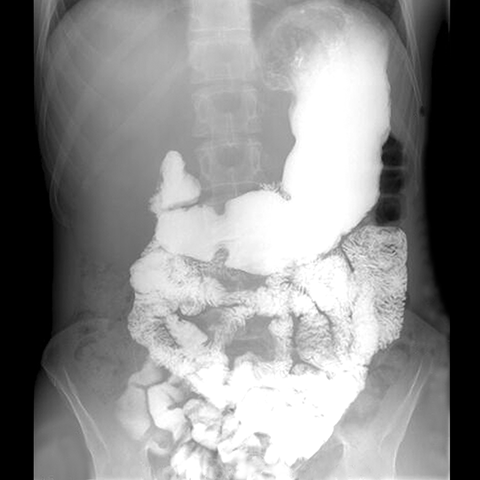

Barium Small Bowel Follow Through, Normal [1 of 3]